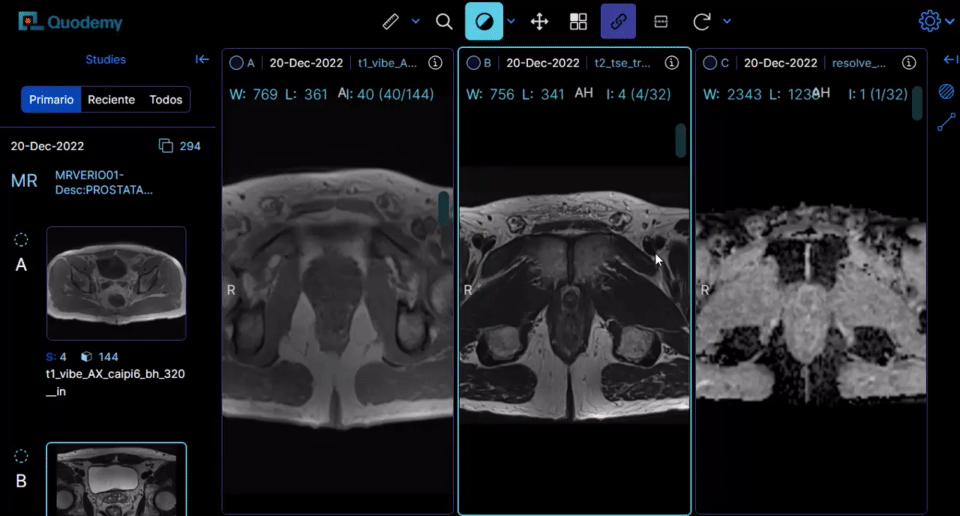

Fórmate con casos reales y diagnosticando directamente con nuestro visor DICOM de última generación.

Por eso, en Quodemy aprenderás con casos reales en visor DICOM, correlacionando la imagen con la clínica, el informe experto y la anatomía patológica.

Curso: Resonancia Magnética y biopsia PROSTÁTICA (2a. Edición)

Curso 100% on-line, con material disponible en todo momento durante el desarrollo del mismo con participación interactiva del alumno. El curso está dirigido a urólogos, oncólogos radioterápicos, oncólogos clínicos y médicos nucleares. El objetivo general del curso es desarrollar habilidades prácticas en la lectura e interpretación de los estudios de RMmp prostática a modo de facilitar la planificación diagnóstica (biopsia) y terapéutica (terapia focal/prostatectomía radical/radioterapia). Así mismo, el alumno conocerá los principales tipos actuales de biopsia prostática, su utilidad y sus limitaciones.